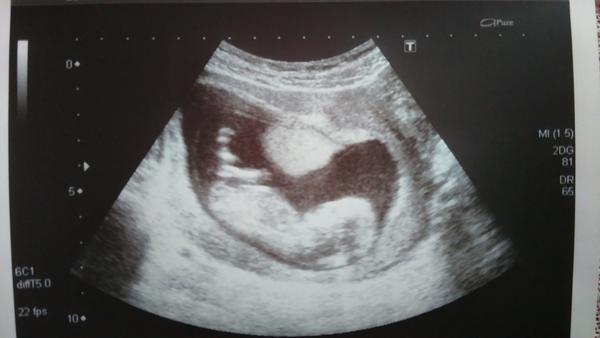

Ahoj maminky a budoucí maminky 😉 Prosím, poradila byste mi některá, co vidíte na fotce z ultrazvuku ve 20. týdnu za pohlaví? Určitě jste foteček viděly už mraky, proto vás žádám o radu...Nechci nikoho ovlivnit, proto svůj tip řeknu později 🙂 Děkuju moc!!!

Tak to asi vypadá na holčičku.

Tipuju kloucka

Ja bych teda rekla jasny kluk,ale mozne je vse 🙂